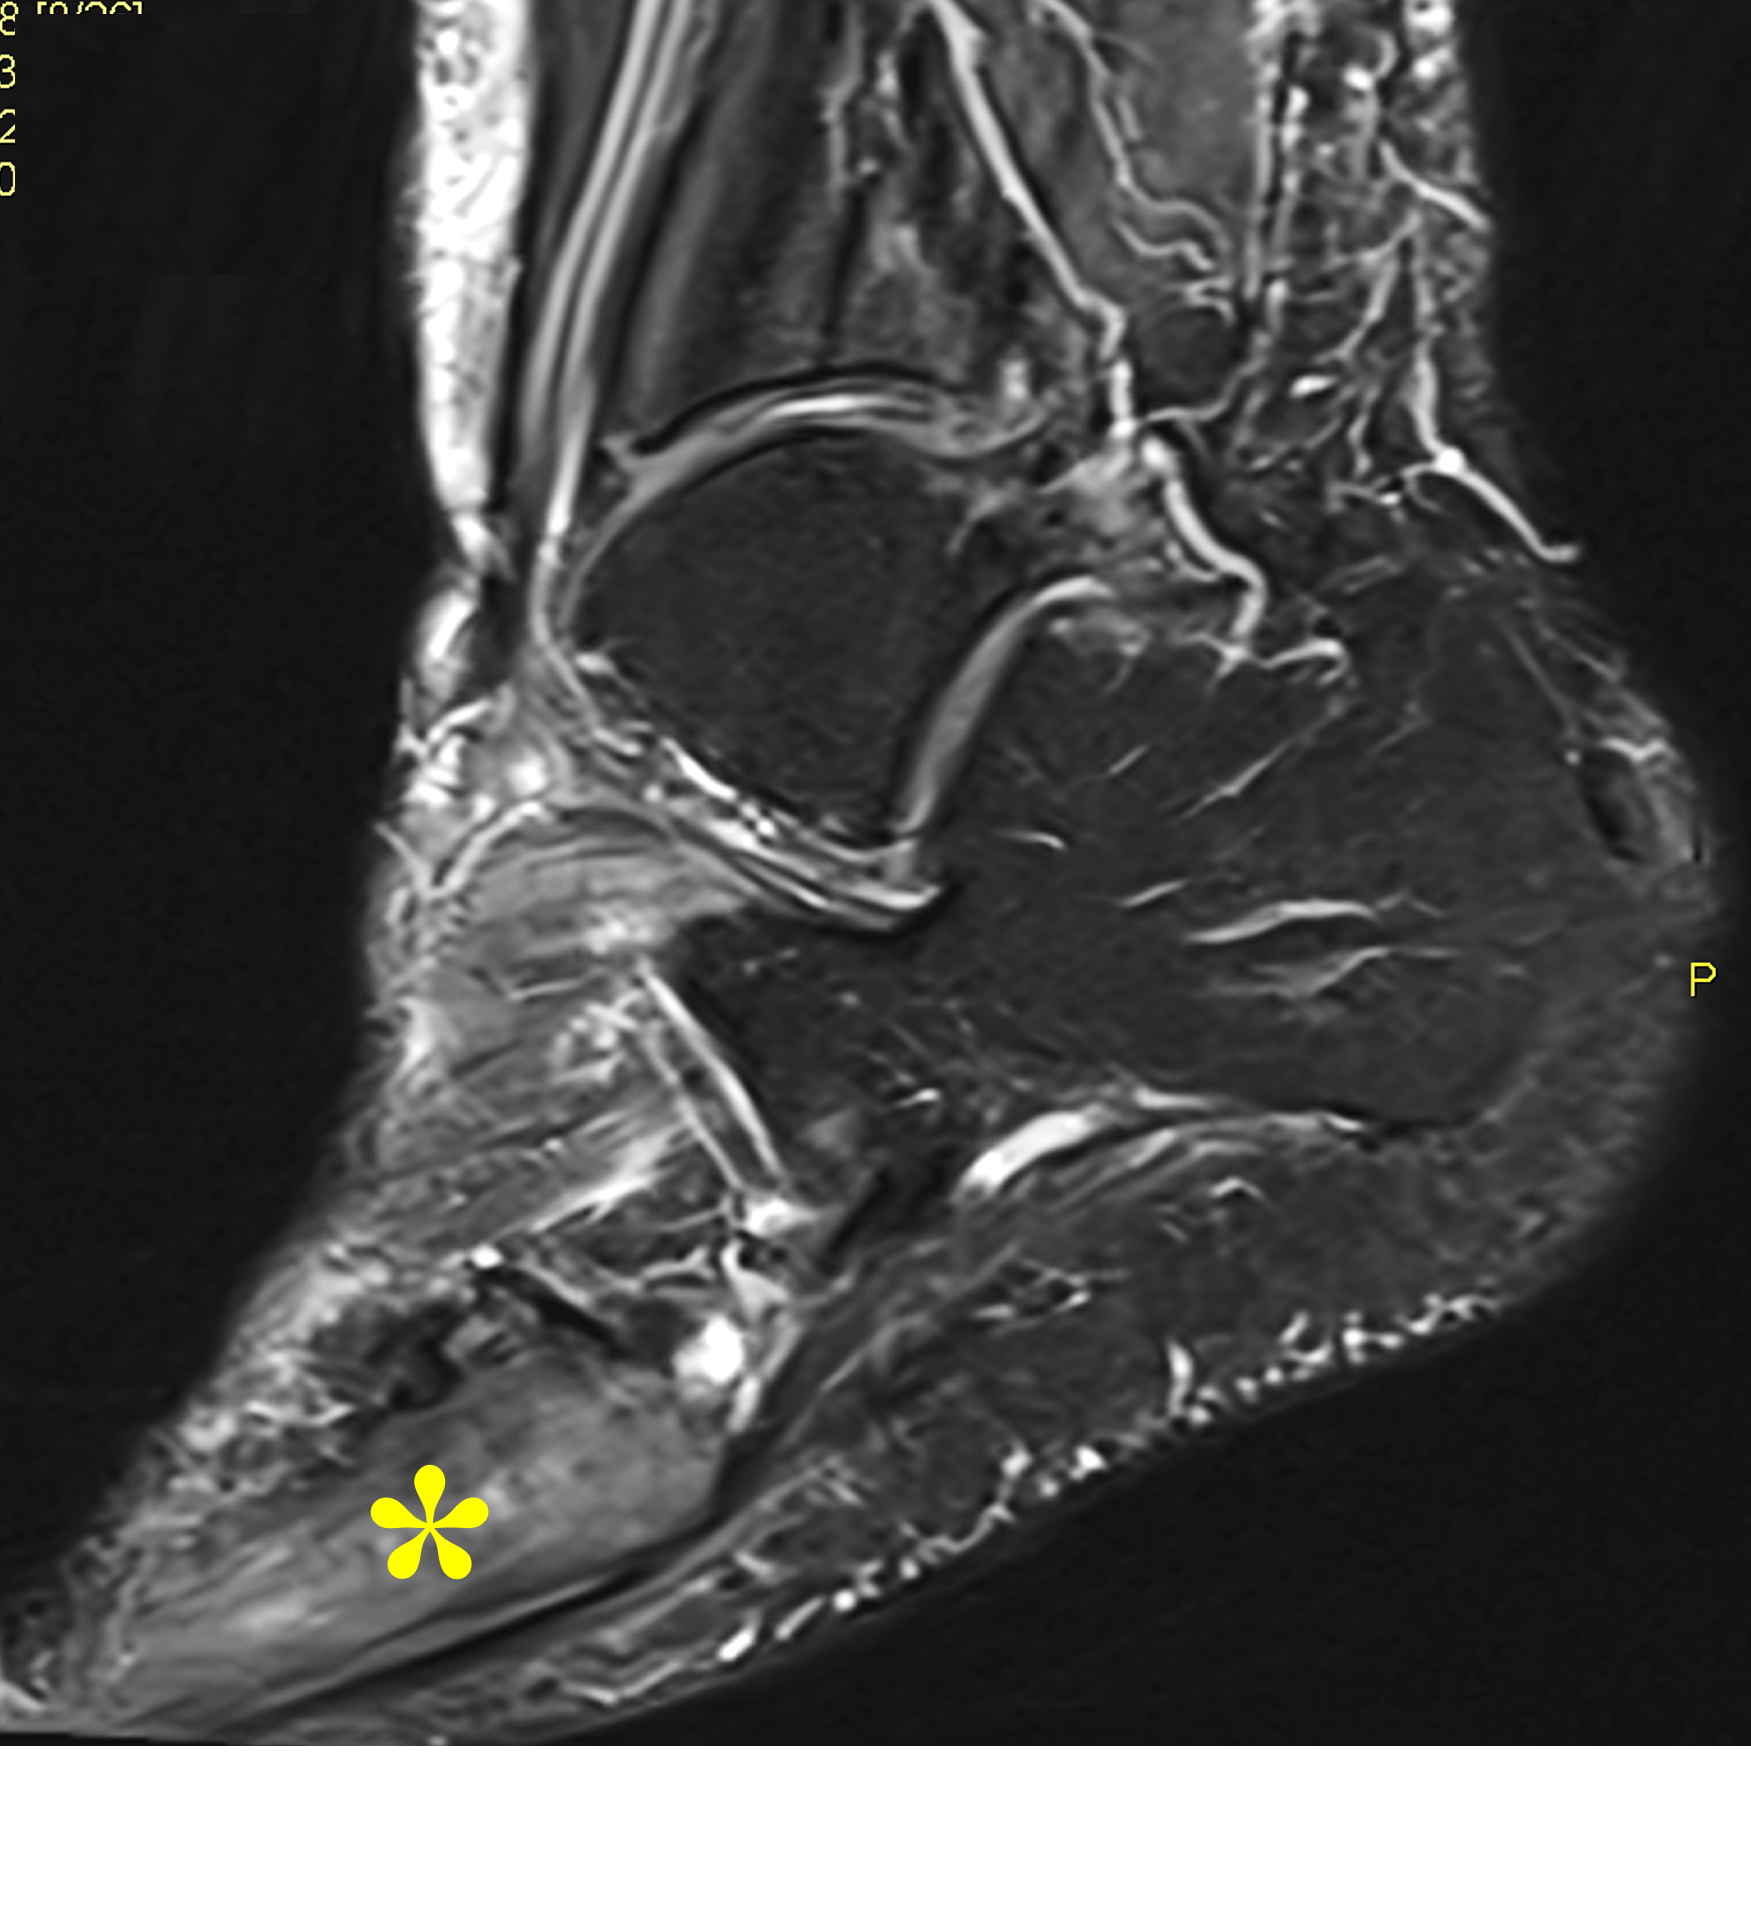

Figure 2: (2A) Sagittal T1-weighted image shows severe thickening of the distal femoral cortex (yellow arrow) and thickening and coarsening of the trabeculae in the femoral condyles (red arrow). Note the high signal intensity fatty marrow in both regions. (2B) Axial fat-suppressed, fluid sensitive sequence through the distal femoral shaft shows severe thickening of the bone cortex, with small round and tubular high-signal intensity foci within the cortex (arrow), likely representing cysts and dilated vascular spaces. (2C) Axial fat-suppressed, fluid sensitive sequence through the femoral epicondyles shows heterogeneous marrow (asterisks), with areas of suppressed marrow fat, mildly increased marrow signal intensity, and small cyst-like lesions. (2D) AP radiograph shows typical findings of mixed phase Paget disease in the distal femur including cortical thickening, course trabeculae, and bone enlargement. Secondary medial compartment predominant osteoarthritis has developed, likely contributing to symptoms.

Figure 9: Sclerotic phase Paget disease of the fifth metatarsal, MRI pattern 3. (9A) Sagittal T1-weighted image shows nearly uniform hypointense marrow in the fifth metatarsal, with small islands of preserved marrow fat (arrows), which helps exclude a malignant process. (9B) Sagittal fat-suppressed T2-weighted image shows mildly increased signal intensity throughout the marrow (asterisk). (9C) Dorsoplantar radiograph demonstrates sclerosis throughout the fifth metatarsal, due to cortical and trabecular thickening. Note the bone enlargement and bowing. (9D) Short-axis CT image shows nearly uniform sclerosis throughout the fifth metatarsal.